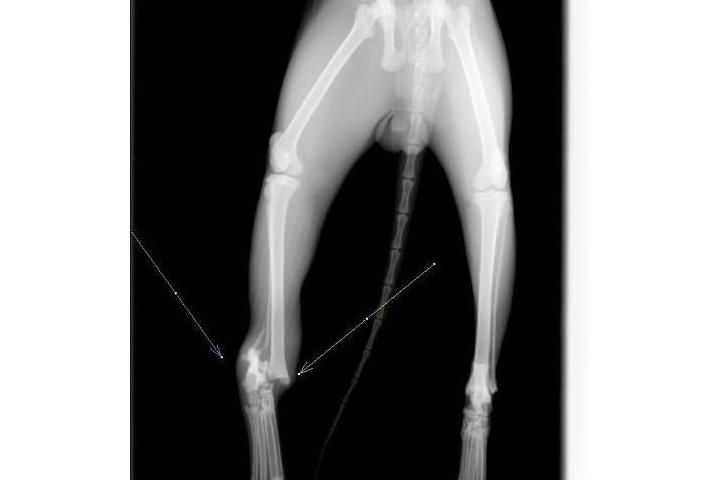

Os subimos la radiografía de Naranja. Tiene una fea luxación tarsal que necesita ser operada. Solo la operación son 192€.

Gracias por ayudarnos a pagar estas cosas con este euro al mes mediante Teaming.

Naranja con su patita operada. Le esperan varios meses de recuperación y todas las semanas tiene que ir a revisión. Gracias por ayudar a la recuperación de Naranja con este euro al mes que salva vidas!